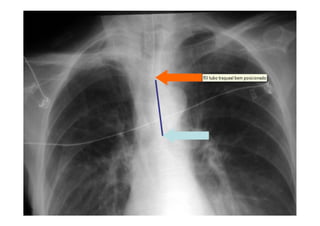

Utiliza-se com frequência p/ avaliar:

O posicionamento do TOT: 4-6 cm acima da carina;

Radiografia e TC de tórax

Avaliação TOT pós intubação:

Posição do TOT

Utiliza-se com frequênciap/ avaliar: O posicionamento do TOT: 4-6 cm acima da carina; Se os pulmões estão sendo aerados adequadamente; Alterações patológicas e diagnóstico de pneumopatias; Outros. Radiografia e TC de tórax

Avaliação TOT pósintubação: Movimento simétrico do tórax Intubação seletiva: Movimento de somente um hemitorax Ausculta simétrica do murmúrio vesicular Intubação seletiva: MV ↓ no pulmão contra lateral Ausência de murmúrio vesicular a nível de estômago Condensação de gás no tubo durante expiração Elevação da saturação de O2 em 30 segundos Posição do TOT